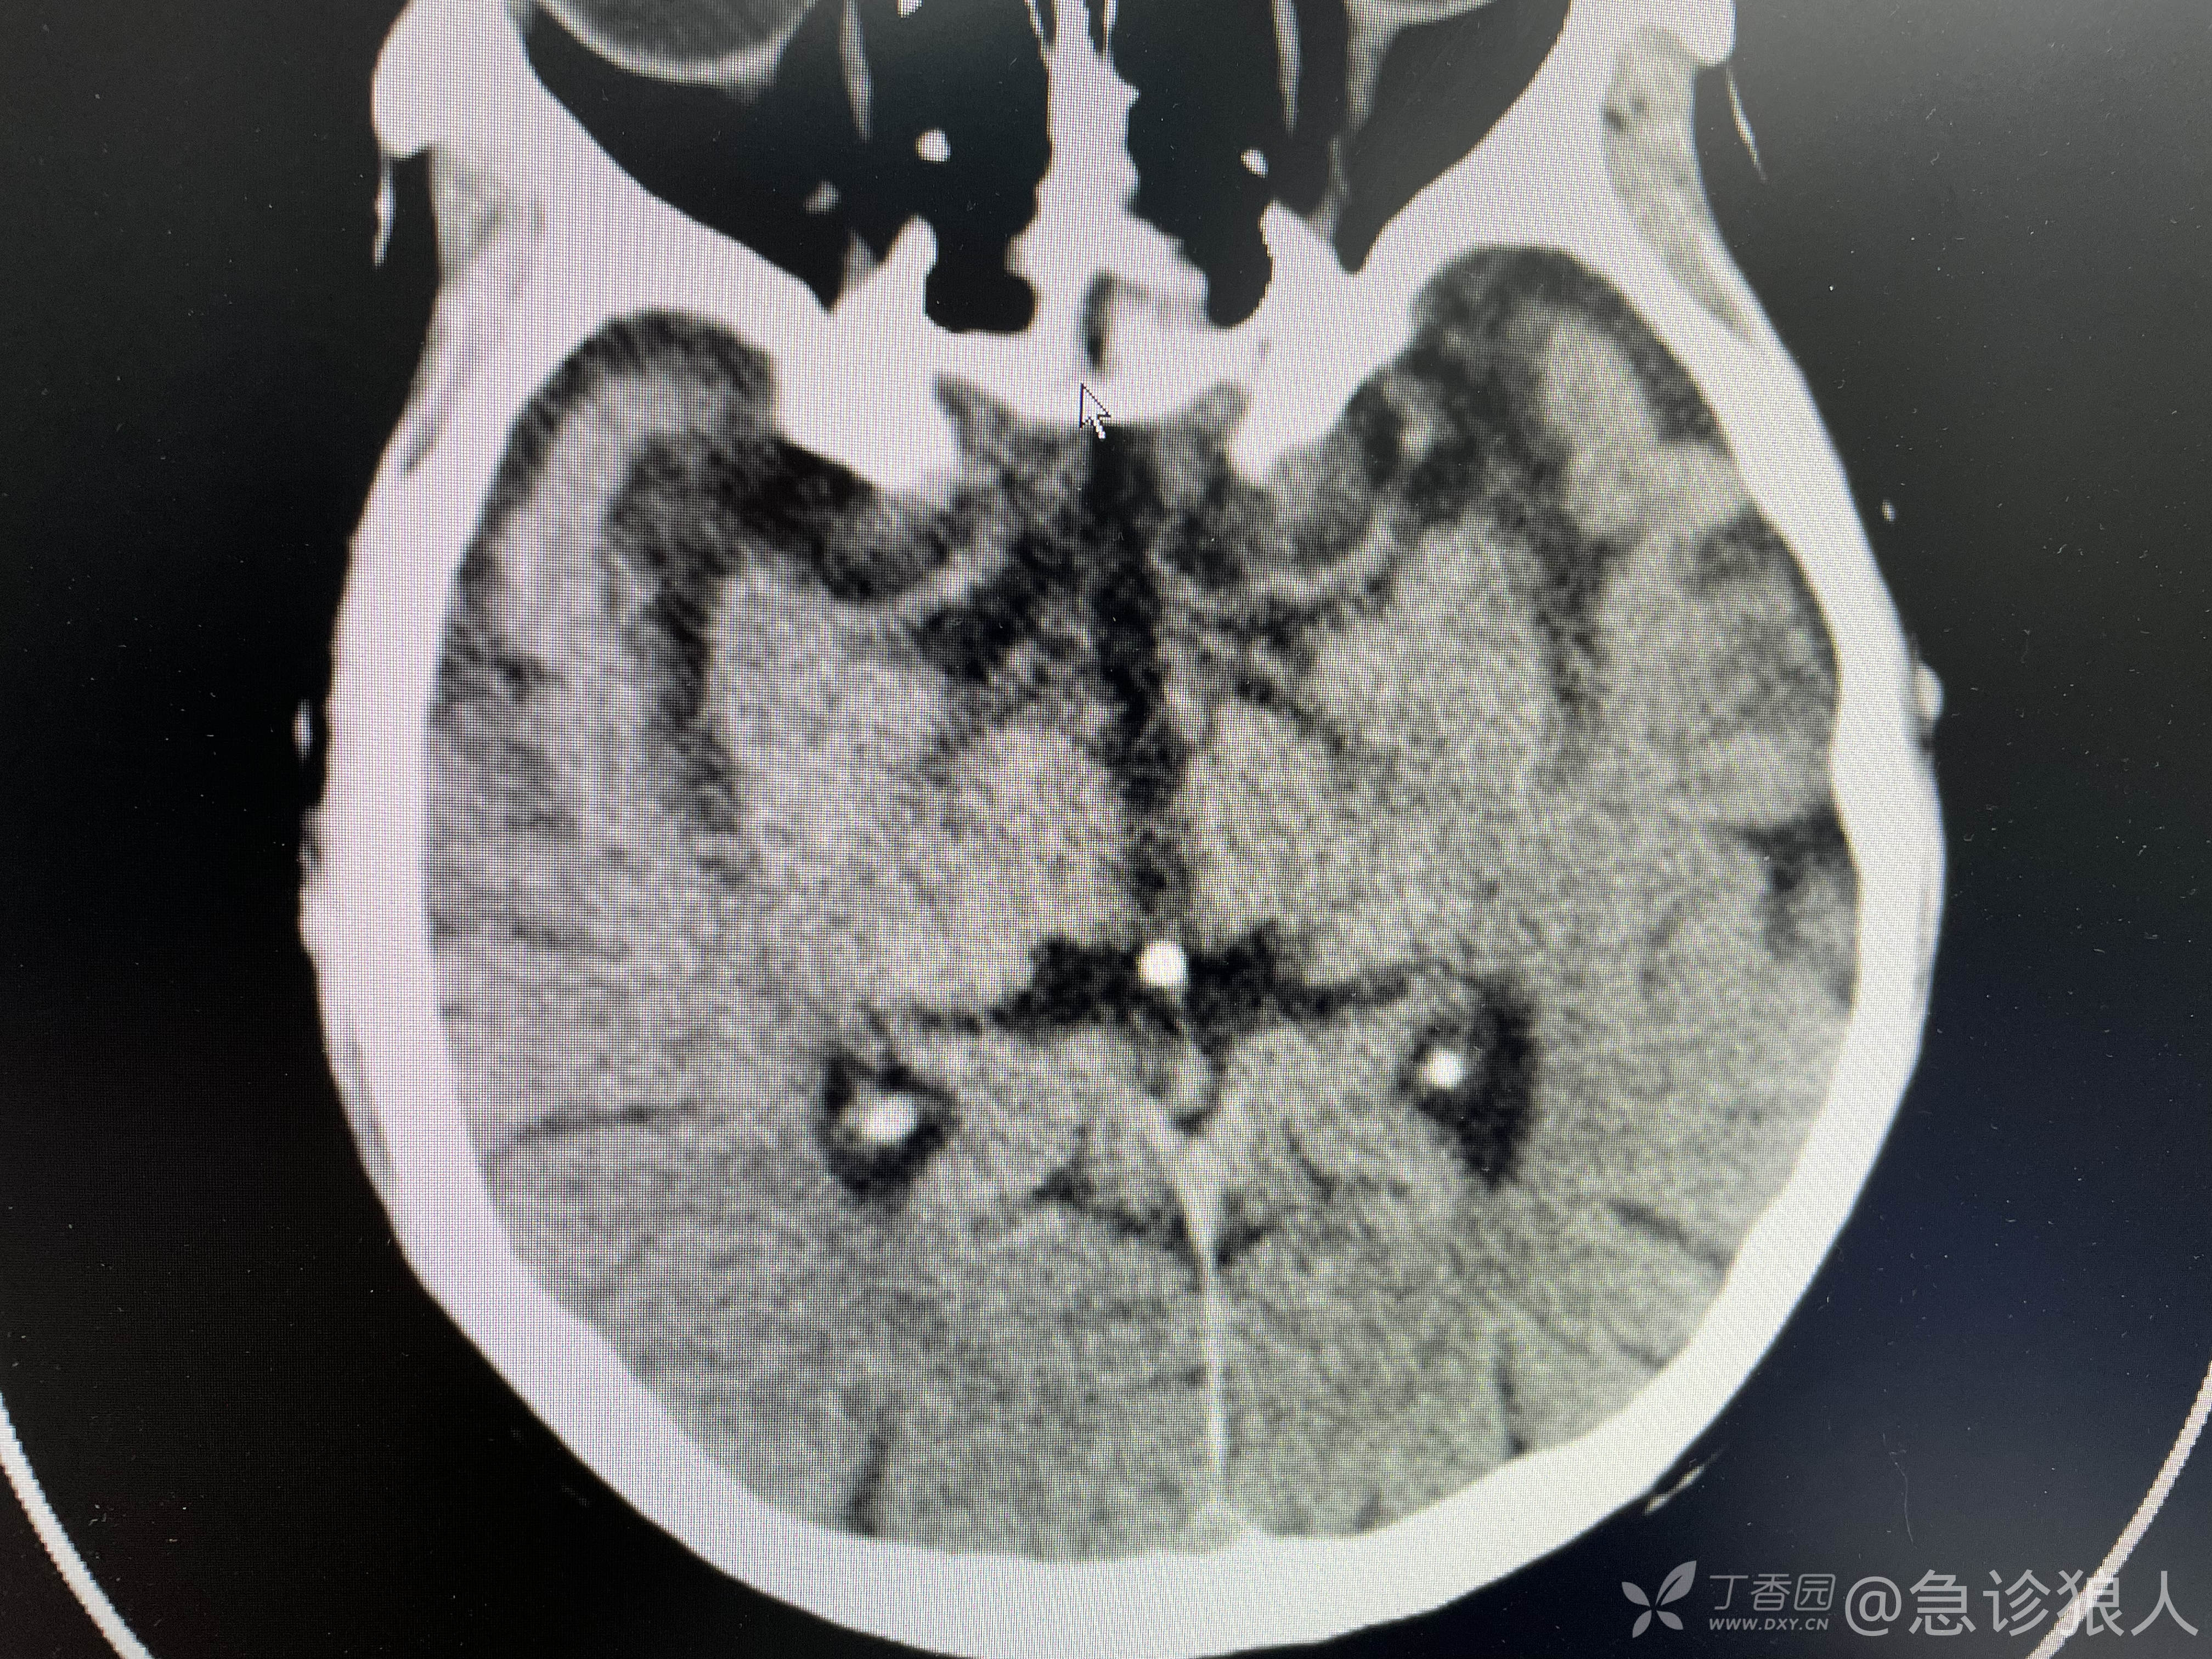

“我有个病人,头晕来的,查了颅脑Ct没事。我给查了个血气,乳酸9.0?”

转身又走回抢救室办公桌旁!打开老人的检查结果说,“心率快,血压低,高乳酸,血小板91都支持休克,DiC!”

继续说,“你看老人肝脏,结构已经改变,肝功能很差了。你把检查该完善的完善了,我就要!”

心率快、血压低、乳酸高、血小板低是支持休克的,但是凝血相对正常,肌酐正常的休克有吗?没有!是可以直接排除的,如果肝功出来,谷草转氨酶正常,就可以直接排除休克。很好理解,休克,外周灌注不足,乳酸中毒,横纹肌溶解,肾前性无尿,凝血的激活,这都是同步出现的。

“肝脏上有没有占位,结构改变了,肝硬化了?”

“我只能报脂肪肝,看不出来其他!”